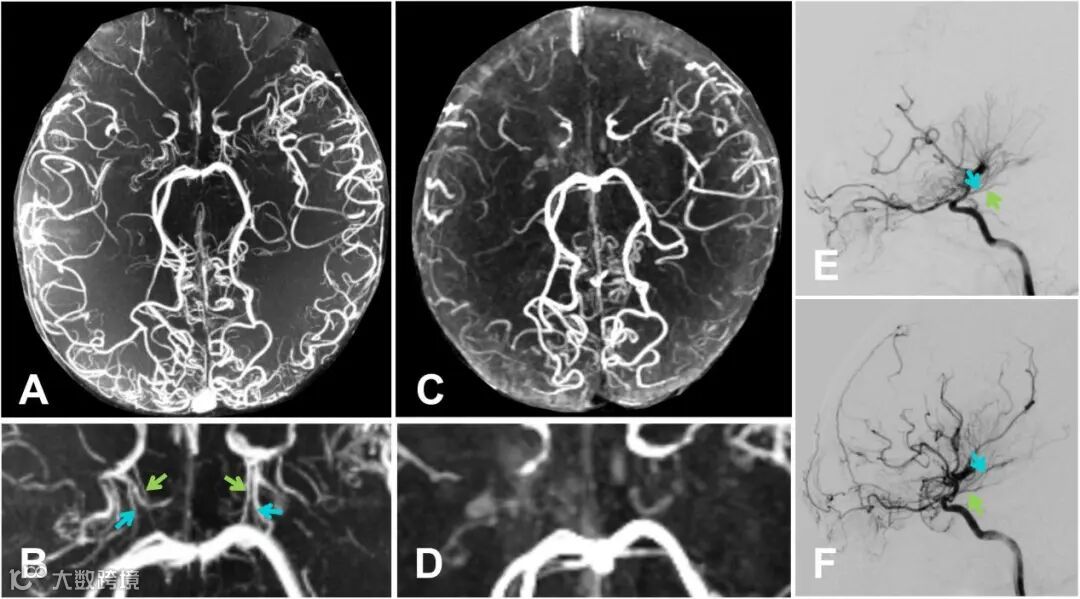

图1 AChA和PComA在7T TOF-MRA上的分级示意图。

(A)0级:AChA不可见或正常(蓝);PComA不可见或正常(绿)。

(B)1级:AChA在脉络膜裂内扩张和延伸(蓝);PComA扩张但无异常广泛分支(绿)。

(C)2级:AChA超出脉络膜裂的扩张和延伸(蓝);PComA扩张伴有异常广泛分支(绿)。

(D)3级:由于颈内动脉闭塞导致AChA和PComA消失(蓝)。

图2 7T TOF-MRA显示出优于3T TOF-MRA的性能,同时对左侧前脉络膜动脉(蓝色箭头)的可视化效果与DSA相当。

图3 展示了7T TOF-MRA(A和B)和3T TOF-MRA(C和D)图像以及DSA图像(E和F)。7T TOF-MRA在AChA(蓝色)和PComA(绿色)的可视化方面优于3T TOF-MRA且与DSA相当。